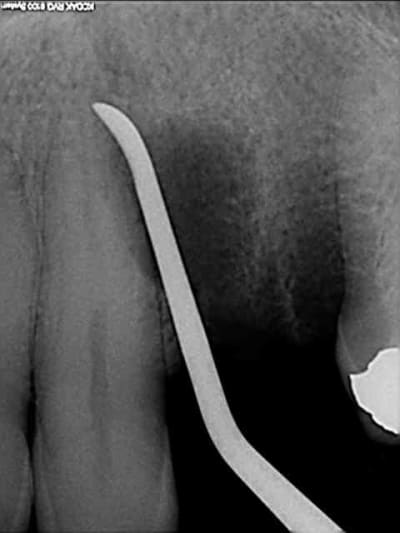

tiens voici des photos de ce matin...

patient avec kyste +++ aux apex et fenestration

je n'implante pas

je comble au Graftec

je met une membrane

je referme

8 mois après,

je vais implanter

comme je suis curieux, j'ouvre large et je regarde;

c'est décevant,le volume est là mais l'os n'est pas génial.

voilà pour les photos...

pendant que je forais, et le patient le sentait également, je sentais et entendais les particules de graftec.

en plus au bout de 8 mois j'aurai espéré trouver quelque chose de mieux non ?